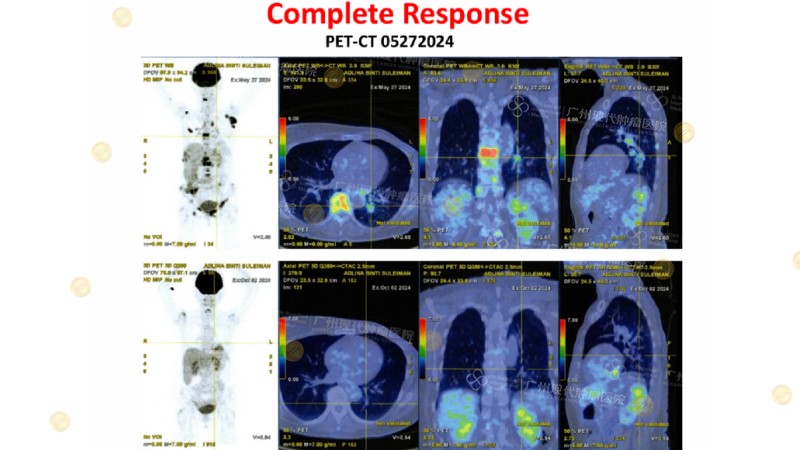

Precise analysis revealed that the patient was HER2-positive, PD-L1-positive, and had a functional disorder. This patient, who had previously undergone a total mastectomy and delayed chemotherapy, developed multiple metastases to the spine, liver, and lungs in 2024. Based on this, a personalized treatment plan skillfully combined targeted therapy and biological therapy, supplemented by continuous metabolic and physiological support. Ultimately, the patient successfully achieved complete metabolic remission (CR) and regained a good quality of life.

(CT shows complete disappearance of the tumor lesion)